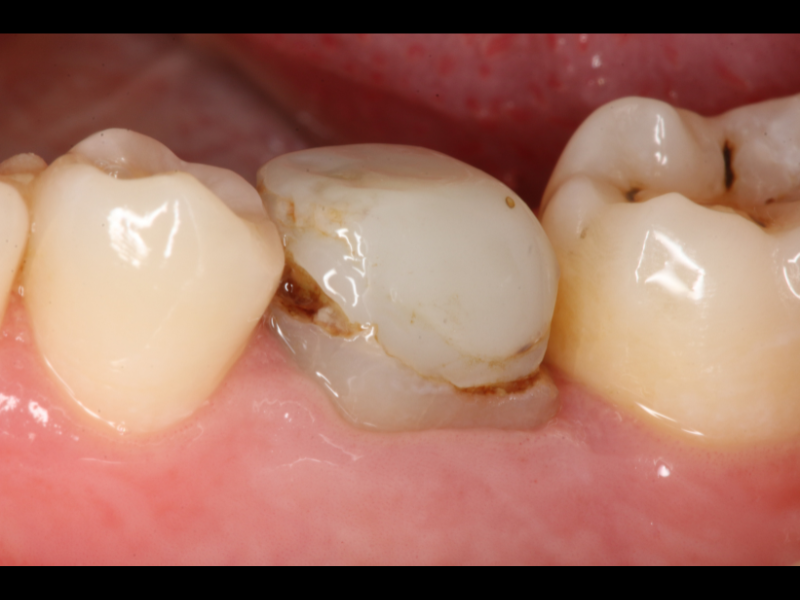

• Ridefinizione di una corretta cavità d’accesso

• Rimozione delle ritenzioni endocanalari: perni metallici e perni in fibra

• Rimozione dei materiali da otturazione canalare: confronto tra diverse tecniche